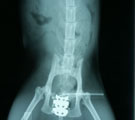

結腸内に巨大な宿便あり 手術所見。プレート設置 直後。骨盤が十分拡幅 術後1ヶ月。普通に歩く。

経過:受診時、レントゲンにて骨盤の恥骨前縁に骨の変形あり骨盤腔側に突出していた。そのため排便障害が生じ結腸内に巨大な宿便がみられた。恥骨前縁の変形は交通事故の影響によるものと考えられた。恥骨部分の突出部を削ったとしても再び術後増殖して再び骨盤腔が狭窄する可能性が高いので、矢田式骨盤拡幅プレート設置を行った。術直後の腹部レントゲンにて秘結便が十分通過できる程度、骨盤が拡幅されていることを確認した。術後経過は極めて良好で、毎日排便がみられるようになった。術後2-3日は軽度開脚して歩行していたが次第に正常歩様になり、1ヶ月後には歩行に何も問題がみられなくなった。